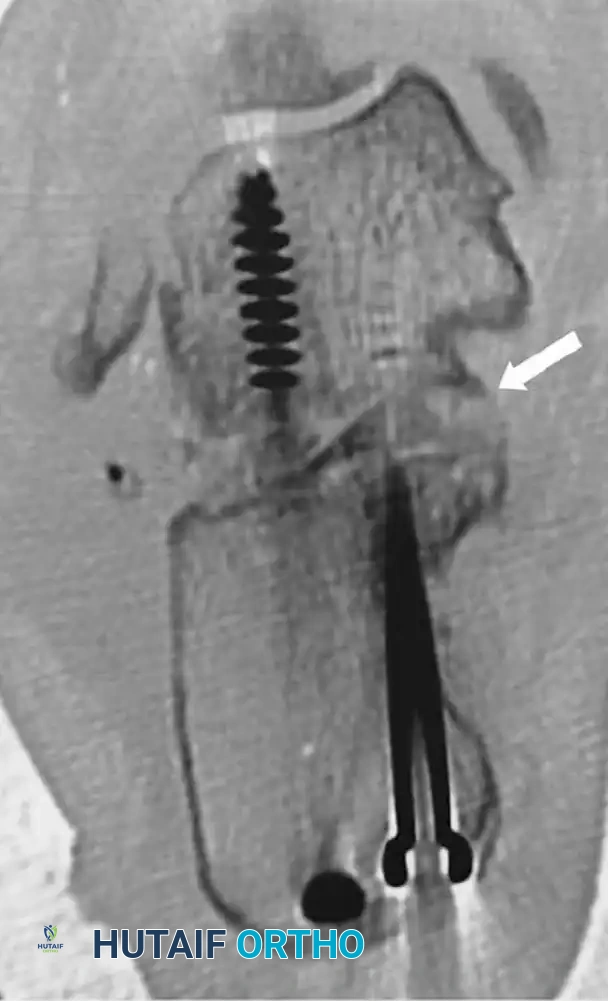

A fine-cut computed tomography (CT) scan with sagittal and coronal reconstructions is the definitive imaging modality. Coronal cuts precisely quantify the lateral wall blowout and the status of the posterior facet of the subtalar joint. Sagittal cuts evaluate the calcaneocuboid joint, which may also be arthritic and require concurrent management.

- Verify the correction of the varus deformity, the restoration of calcaneal height, and the decompression of the subfibular space using intraoperative fluoroscopy (AP, lateral, and Harris axial views).

- Definitively fix the subtalar arthrodesis using two or three large-diameter (6.5 mm or 7.3 mm) cannulated, partially threaded cancellous screws. Insert the screws from the calcaneal tuberosity, directing them anteriorly and superiorly into the body and neck of the talus to achieve maximal compression across the arthrodesis site.